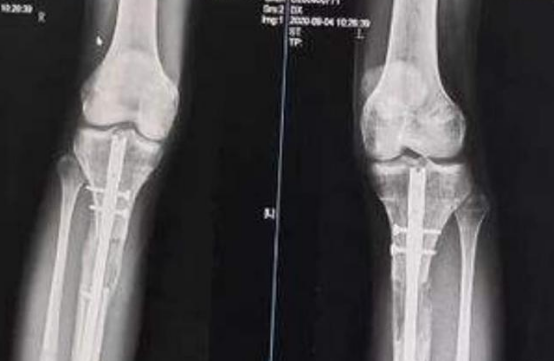

在做手术之前,医生给他进行全面的检查,最终确定术后会增加7.5厘米。

2014年9月24日,李亚诺怀着重生的心,进入了手术室。

这场手术进行了好几个小时,手术结束后,李亚诺被平安地推了出来,

医生告诉他的父母,手术很成功,

如果术后恢复得不错,明年他的身高就能达到174厘米。

在复查的时候,医生告诉他们李亚诺还要做一次手术,这次手术做完后,应该会恢复的不错。

就这样,20岁的李亚诺再次躺进手术室,这一次手术过程进展得很顺利,

然而术后李亚诺的恢复却不为理想。

在拆掉腿部支架后,他的腿部肌肉出现了病变,他再也不能像正常人一样走路了。

更遗憾的是,他有时候连站都站不起来。

慢慢的,他的腿部出现变形,脚部也出现问题,总之他的恢复很糟糕。